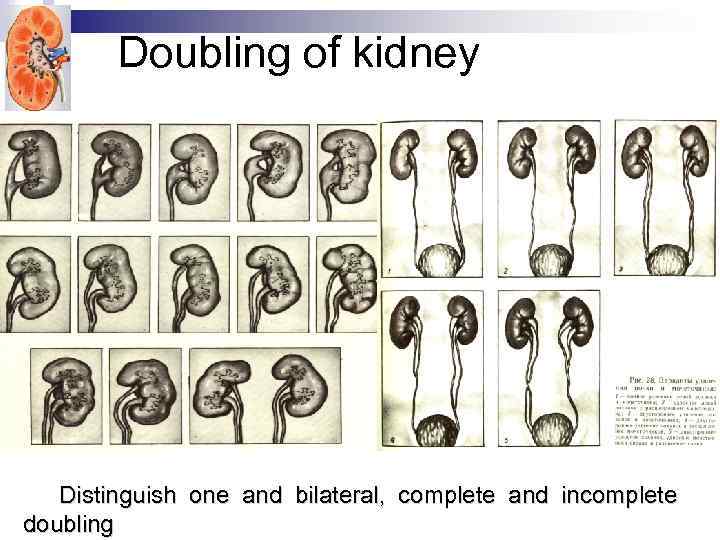

Doubling of kidney Distinguish one and bilateral, complete and incomplete doubling

Doubling of kidney Distinguish one and bilateral, complete and incomplete doubling